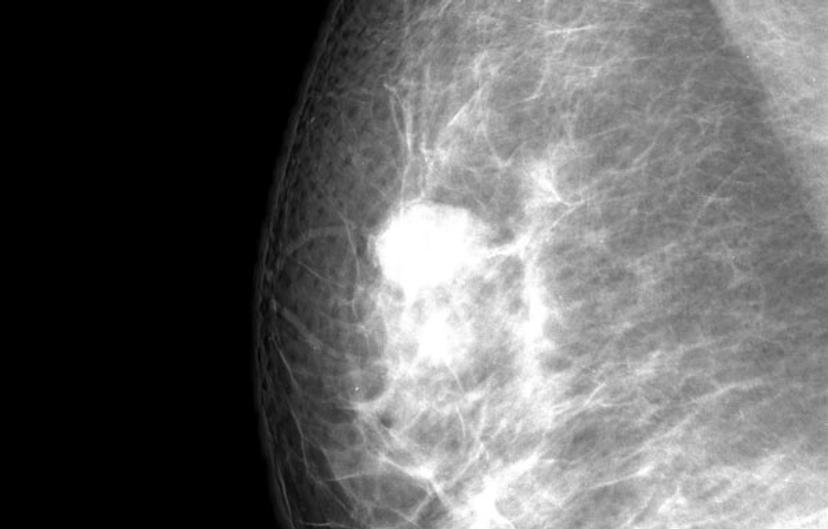

Image of a breast mammogram used to detect breast cancer

Approximately 1 in 4 breast cancer patients are positive for human epidermal growth factor positive (HER2+)2. HER2+ is present on the surface of normal breast cells, however HER2+ patients have very high numbers of these receptors which stimulate the cancer cells to divide and grow. Targeted therapy with Herceptin can be very effective in HER2+ patients. Herceptin attaches itself to the HER2 receptors and blocks them from receiving growth signals thus stopping or slowing the tumor growth. Herceptin therapy cannot be prescribed unless the patient has been tested to check there HER2 level.